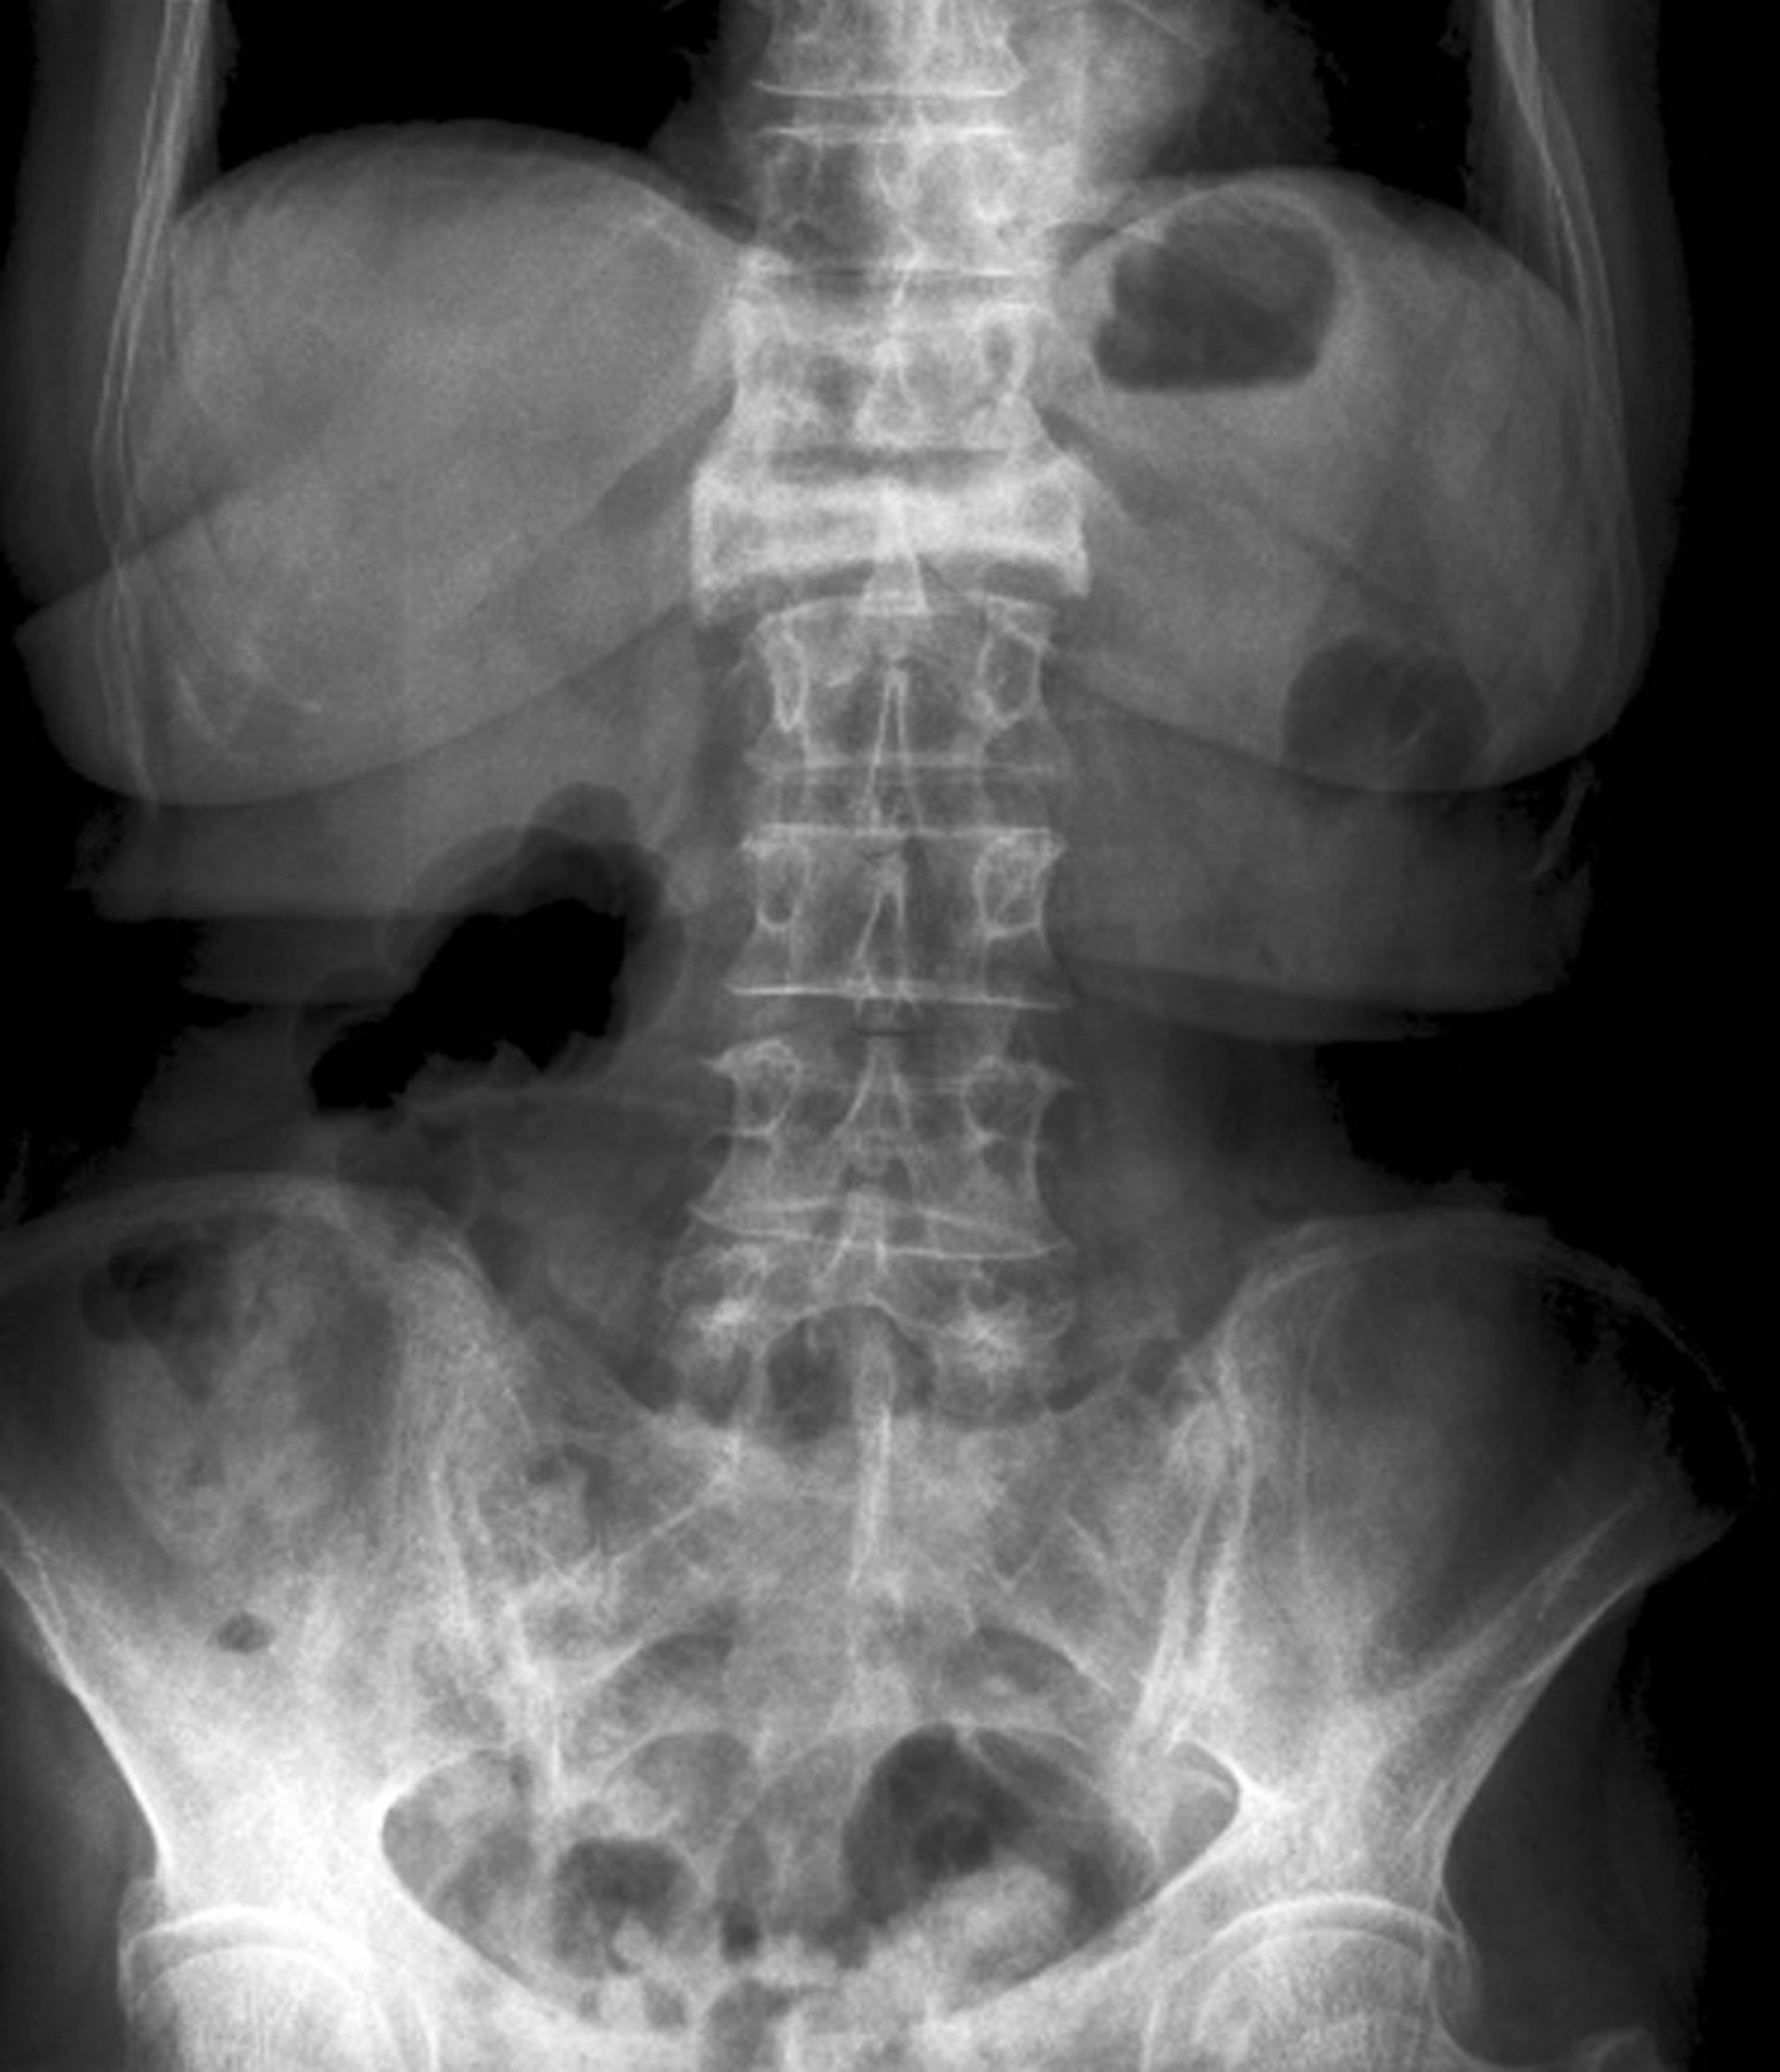

重度の圧迫骨折の前後像

この第1腰椎の圧迫骨折は,前後像で重度の椎体高減少および放射線不透過性の亢進として視認できる。